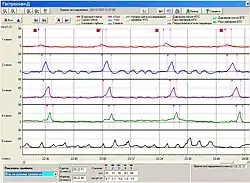

Исследование кислотности верхних отделов ЖКТ

Внутрижелудочная pH-метрия играет важнейшую роль при диагностике и лечении кислотозависимых заболеваний, при исследовании гастроэзофагеальных, дуоденогастральных, фаринголарингеальных рефлюксов. В клинической практике нашли применение несколько методов внутрижелудочной pH-метрии:эндоскопическая (длительность измерений 5 минут), экспресс-pH-метрия (около 30 минут), кратковременная стимулированная (до 2—3 часов) и длительная (24 часа и более) pH-метрия. pH-метрия также применяется для оценки действия кислотоподавляющих препаратов. Измерения выполняется с помощью специальных pH-метрических зондов, вводимых пациенту перорально (при кратковременной pH-метрии), трансназально (при суточной pH-метрии)[21][23], через инструментальный канал эндоскопа (при эндоскопической pH-метрии)[24] или с помощью прикрепляемых к стенке пищевода pH-метрических капсул[25]. Исследование некислых рефлюксов выполняется с помощью импеданс-pH-метрии пищевода[26]. Для дифференциальной диагностики загрудинных болей неясной этиологии применяется гастрокардиомониторинг — одновременное исследование кислотности ЖКТ и электрокардиограммы[21].

- pH-метрия верхних отделов ЖКТ

Ацидогастромонитор для суточной pH-метрии пищевода и желудка

Ацидогастромонитор для суточной pH-метрии пищевода и желудка 24-х часовая pH-метрия пищевода (фрагмент pH-граммы больного ГЭРБ)

24-х часовая pH-метрия пищевода (фрагмент pH-граммы больного ГЭРБ) pH-грамма желудка при подборе ингибиторов протонной помпы

pH-грамма желудка при подборе ингибиторов протонной помпы Прикрепляемая к стенке пищевода капсула «Bravo» для исследования ГЭР

Прикрепляемая к стенке пищевода капсула «Bravo» для исследования ГЭР

См. также